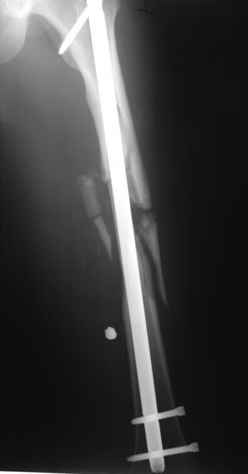

В приложении пример огнестрельного ранения бедра, оперированного на 2 сутки после ранения.

Штифтование было выполнено только на вторые сутки по причине задержки перевода из другого госпиталя, АБ профилактика была начата в другом учреждении, с момента госпитализации пациента к ним. Входное пулевое отверстие и зона введения штифта зажили первичным натяжением.

Единственно что наблюдал - замедленная консолидация, судя по серийным Рг граммам. В приведенном случае прии вялом мозолееобразовании сделал ошибку, решившись динамизировать гвоздь - перелом сросся со значительным укорочением бедра - повторная хирургия по удлинению бедра и проксимальным запиранием, больной мобилизован и вполне доволен(кстати заметить больной с ВИЧ инфекцией - изначально скомпрометированный иммунитет и несмотря на это, всё прошло без костной и мягкотканной инфекции.